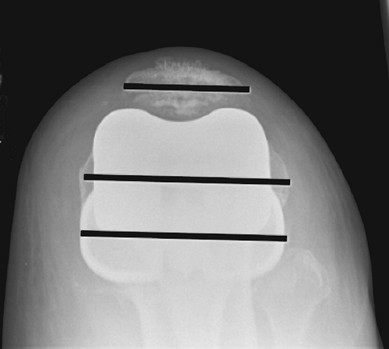

not very reliable (Fig. 26-5). Postoperatively,

the patellar axis should be parallel to the transepicondylar axis and

the tibial axis. Skyline views in 50 to 70 degrees can demonstrate

appropriate alignment (Fig. 26-6). An

![]() |

|

Figure 26-6 Skyline view demonstrating patellar axis, transepicondylar axis, and tibial long axis being parallel.

femoral component size, and the anterior cut is completed. Figure 26-4 shows the positioning of a tensiometer in combination with

a cutting block to demonstrate how an equal flexion gap could be created using this technique.